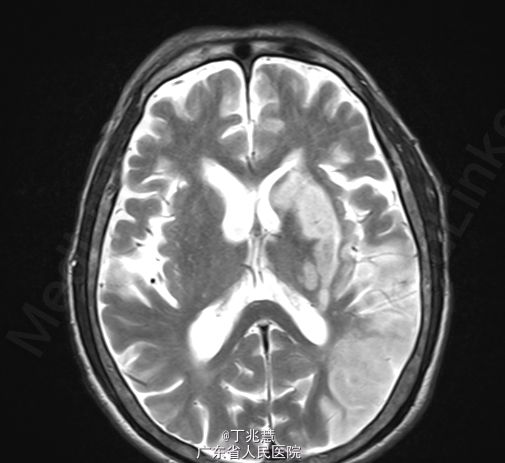

女性,46岁。因“反复发热、头痛2月”入院。患者自2个月前无明显诱因出现头痛,呈持续性,起病初期头痛程度轻,可忍受,自服药治疗(具体用药不详)病情未见好转,且头痛程度逐步加重,难以忍受,无恶心,呕吐,无肢体抽搐,间中有发热,体温最高可达39.2摄氏度。 既往糖尿病史5年,控制不佳。

查体:心肺腹查体未见异常。神经专科:右侧上下肢肌力0级左侧上下肢体肌力5级。 颈强直,颏胸距4横指,双侧Kernig征(+)。

诊断:结核性脑膜脑炎; 治疗:抗结核治疗。

随访:患者转胸科医院进一步治疗,具体不详; 讨论:结核菌一般侵犯脑膜多见,较少累及大脑实质,本例患者累及脑实质,有肢体无力表现。经规律抗结核治疗后预后相对良好。